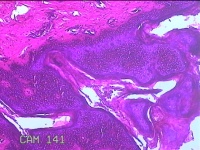

性别

女

年龄

45岁

临床诊断

四肢皮脂腺囊肿

一般病史

发现右侧大腿结节半年余。

标本名称

右侧大腿结节

大体所见

灰白暗红色组织1.5x1x0.8cm一块,表面带梭形皮肤1.3x0.7cm,皮下见结节1.3x1x0.7cm一个,切开结节呈实性,切面灰白 暗红色,质软。

图1